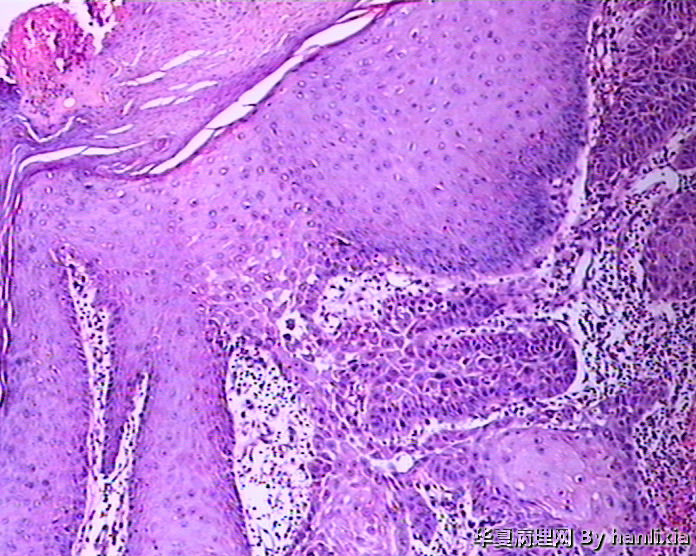

男性患者,50岁,发现面部皮肤(耳旁)肿物一年余,色黑。

图1

图2

图3

图4

图5

图6

图7

图8

图9

图10

图11

图12